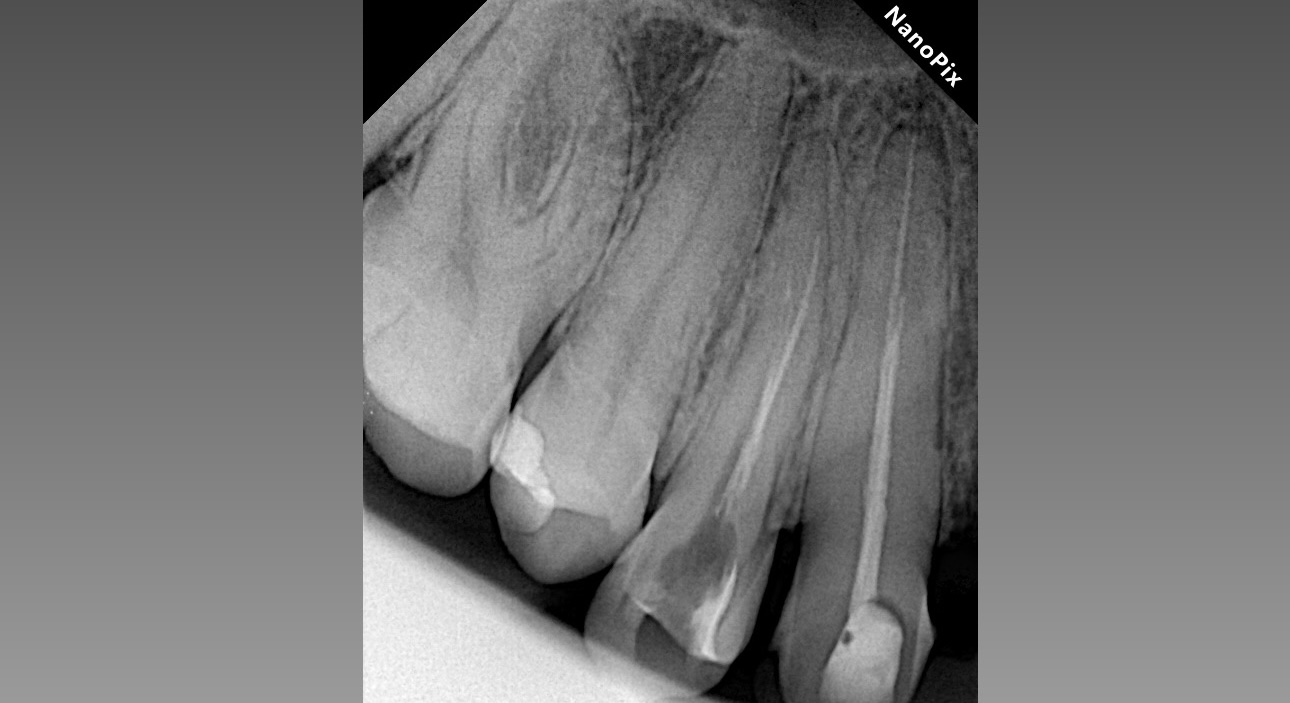

Дезобтурация Sani retreatment. Важно работать от корональной трети, постепенно двигаясь в апикальном направлении. Не стремиться сразу пройти на всю длину канала.

Инструментация Soco SC до 45/04. Финишный инструмент до чистых опилок на кончике файла.

Ирригация 3% NaOCl с УЗ активацией + 17% ЭДТА.

Обтурация биокерамическим силером с гуттаперчей. Автор: Диана Кипарисова